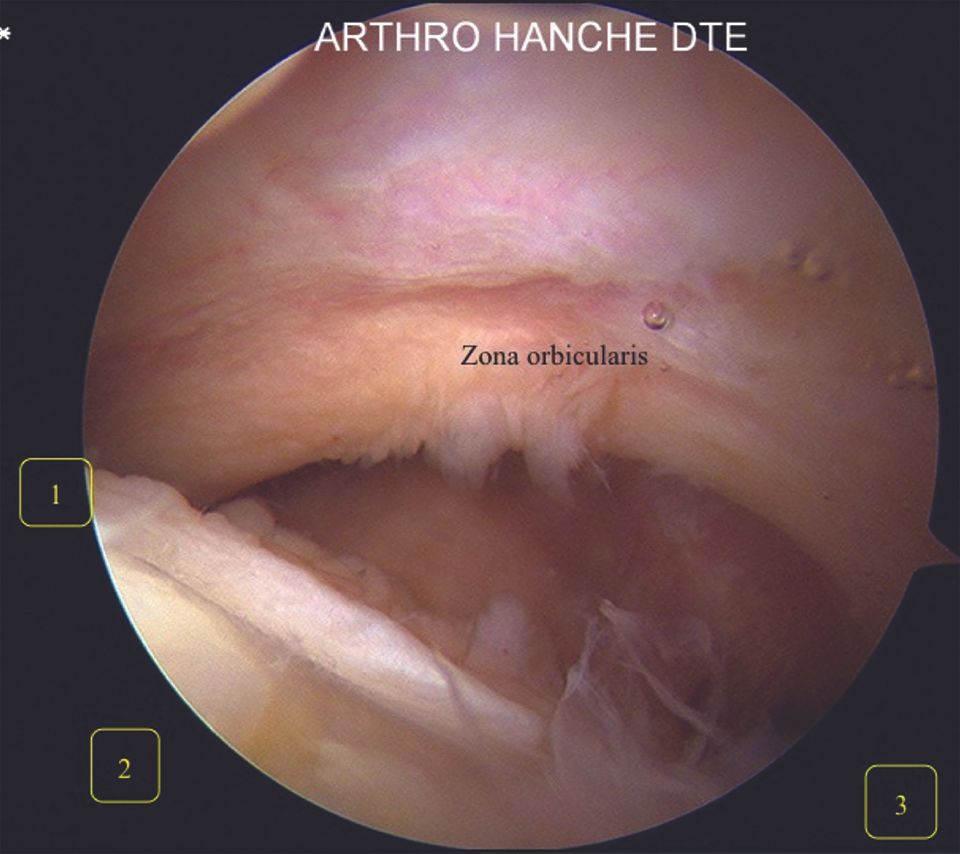

The peripheral compartment is explored (Fig. 14) noting the following anatomic structures: the endocapsular portion of the femoral neck, the zona orbicularis (capsular reflection zone separating the medial and lateral peripheral compartments), the non-weight bearing cartilaginous part of the femoral head and the lateral labrum (Fig. 15), the anterolateral part of the femoral head–neck junction (Fig. 16) and the femoral neck (quadrant 3 in Fig. 14).